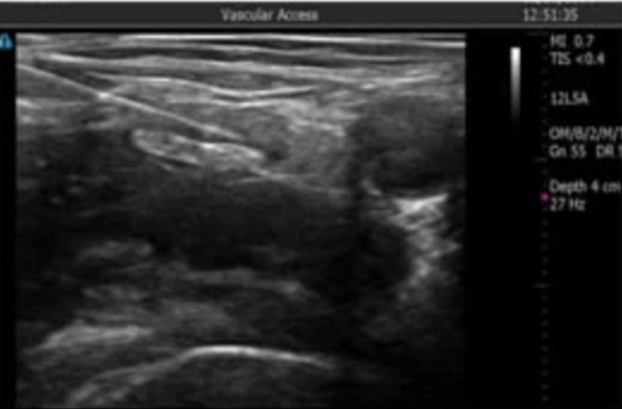

Hình ảnh gây tê thần kinh đùi

Gây tê thần kinh dưới hướng dẫn siêu âm là phương pháp tiêm thuốc gây tê vào các bao dây thần kinh dưới hướng dẫn siêu âm giúp giảm đau. Việc áp dụng kỹ thuật gây tê thần kinh dưới hướng dẫn của siêu âm đã đem lại nhiều lợi ích cho người bệnh và nhân viên y tế.

Quá trình thực hiện, dưới hướng dẫn của siêu âm, các bác sỹ Gây mê hồi sức xác định chính xác dây thần kinh cần gây tê. Dùng kim chọc chuyên dụng cho thuốc tê đi vào thân thần kinh, tránh chọc vào mạch máu. Bơm thuốc tê và đánh giá diện phong bế của thuốc tê. Nhờ đó giảm thiểu được các tai biến, biến chứng như tổn thương dây thần kinh, tiêm thuốc vào mạch máu gây ra ngộ độc thuốc t, tiêm thuốc không đúng vị trí dẫn đến thất bại trong kỹ thuật.